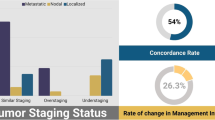

CT and MRI can help determine whether lymph node (LN) metastasis is mainly based on the size and shape of the LNs. However, the rate of misdiagnosis of LNs with normal-sized metastasis is very high. Therefore, both the imaging methods have very low sensitivity for the detection of LN metastases. The specificity of the two methods for the detection of LN metastases is also low. Moreover, the rate of misdiagnosis is higher, because lymphadenopathy may be caused by benign diseases, such as inflammatory hyperplasia of the LNs. Metastases of BC, such as LN metastasis, also have metabolic properties similar to those of the primary tumor; therefore, LNs or distant metastatic lesions with high metabolic activity outside the bladder are detected by PET (Fig. 5.3). A recent meta-analysis of FDG-PET/CT for BC staging and re-segmentation found that the sensitivity, specificity, and accuracy of PET/CT for BC staging were 82%, 89%, and 92%, respectively [3]. In 20–40% of patients, FDG-PET/CT detected more malignant diseases than conventional CT/MRI, and FDG-PET/CT may change the clinical treatment plan in 68% of patients [4]. Some authors believe that FDG-PET/CT diagnosis of LN metastasis is not significantly better than CT. Swinnen et al. reported that the accuracy, sensitivity, and specificity of FDG-PET/CT for diagnosing LN metastasis of BC were 84%, 46%, and 97%, respectively [5]. The corresponding values when CT results were analyzed separately were 80, 46, and 92%. The study considered that compared to CT alone, the combination of FDG-PET/CT afforded no advantage in the staging of invasive BC and LN metastases.

Many clinical studies have assessed the use of FDG-PET/CT for prostate cancer re-segmentation. Most of these studies compared FDG to another PET tracer. Garcia et al. [18] studied 38 patients and found that FDG-PET/CT diagnosed recurrent lesions with a sensitivity of 34% and 11C-choline PET/CT showed a sensitivity of 68%. Therefore, the researchers concluded that FDG-PET/CT has limited value for prostate cancer re-segmentation. However, a study by the National Cancer PET Registry is worth mentioning in this context. This study used scans for pathologically confirmed cancer patients to determine the stage or suspected recurrence (Fig. 5.11). A total of 40,863 FDG-PET and FDG-PET/CT scans were included, of which 5309 were performed in men with prostate cancer (i.e., 2042 for initial staging, 1477 for re-segmentation, and 1790 for suspected recurrence) [19]. These scans resulted in an expected cancer treatment change in 35.1% of cases: 25.3% from untreated to treatment and 9.7% from treatment to untreated. The rates of staging, reclassification, or detection of subgroup changes in treatment plans due to suspected recurrence were 32.0%, 34.0%, and 39.4%, respectively.